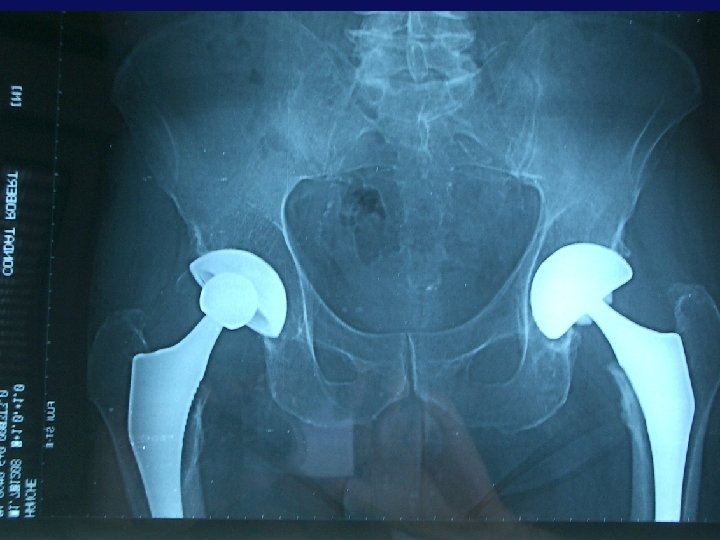

Série récente de 102 C 2 M (98 patients) • Du 11/06/1999 au 30/01/2005 • Répartition: 1 en 1999 13 en 2002 51 en 2003 31 en 2004 6 en 2005 • Pendant la même période implantation de 365 PTH (1/01/2002 à 30/01/2005) • Soit 27% de C 2 M • 59 femmes - 43 hommes

Implants utilisés: • • 80 Saturnes 10 Collegia (Crémascoli) 7 avantages (Biomet) 5 Hades (Dedienne-santé)

Indications: Première intention: • 84 coxarthroses • 4 nécroses • 7 fractures du col fémoral Reprises: • • 3 descellements 2 ostéolyses sans descellement 1 fracture sur PTH 1 luxation récidivante

Toujours Voie d’abord Postérieure 7 Mini invasives 1 Trans-fémorale 56 côtés droits 46 côtés gauches 85 fois réinsertion des P. T. 75 fois suture capsulaire + réinsertion des P. T.

Positionnement: • 67 avec peu au pas • 100 à 45° incl. d’AV ( « dans le cotyle • 2 Verticalisés (>45°) osseux » ) • 35 AV normale (10 à 15 °) • Aucun à plus de 15° d’A. V.

Tenue de l’implant: • Dans tous les cas de la • 64 en os sous chondral série: • 32 en os sous chondral et os spongieux • 6 en spongieux jugé stable après impaction

13 Greffes osseuses associées: • 11 autogreffes ou Allogreffes (cryo conservée) • 2 substituts (TCP -HAP) • 5 reprises dont: • 2 avec greffe massive

Couple de frottement: • 79 Métal / PE • 23 Céramique / PE

Complications précoces: • 1 douleur du psoas • • Avec débord ant cupule constaté traité avec succès par infiltration • 1 fracture parcellaire cotyle • 1 décès (fract. du col) • Pas de luxation • Pas de descellement précoce • Pas d’ostéolyse précoce • Pas de sepsis • Aucune reprise